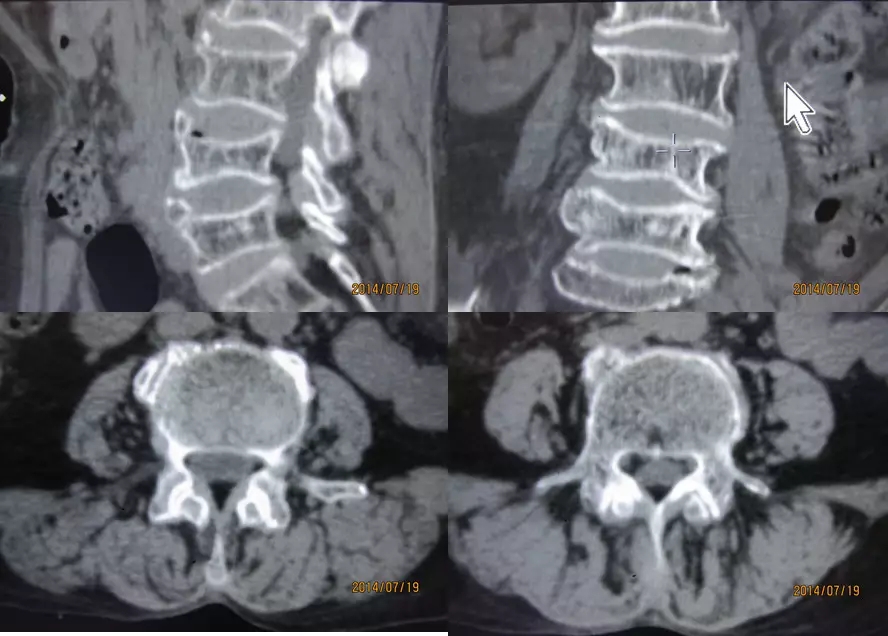

L1-L5、L5-S1正常椎间盘

椎基静脉影

椎间孔前为椎体,后为椎小关节,上下为椎弓根,内与侧隐窝相连,有脊神经根通过。

侧隐窝:向下外续于椎间孔,有脊神经经过:前壁为椎体后外缘;后壁为上关节突前面与黄韧带;外界为椎弓根。

正常前后径为3-5mm,<3mm侧隐窝狭窄>5mm,肯定不狭窄。

腰段横断面解剖及影像

1.经腰椎椎弓根的横断层面(CT)

2.经腰椎椎体下部的横断层面(CT)

3.经腰椎椎间盘的横断层面(CT)